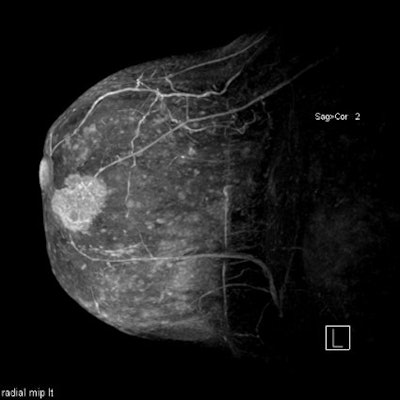

The typical breast MRI performed at First Hill begins with a series of T1-weighted images using fat saturation, followed by a bolus of gadolinium contrast and a second series of images acquired over time. Digital subtraction produces a high-contrast image that allows creation of a maximum intensity projection (MIP) image.

| This 3-D, high-resolution maximum intensity projection (MIP) image illustrates the relationship between tumor and nipple, a key consideration in determining whether lumpectomy or mastectomy is required. Image courtesy of Dr. Bruce Porter, First Hill Diagnostic Imaging. |